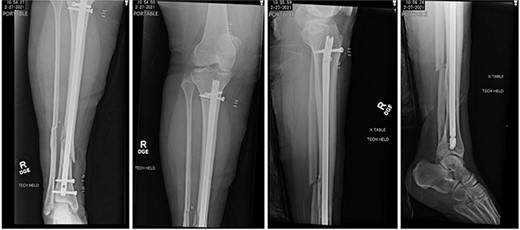

At 2 weeks post-op, the patient was managing pain well, and she demonstrated appropriate range of motion and strength. At 6-week follow-up, however, she complained of diffuse, painful grinding in the right knee which impaired her ability to ambulate. Physical exam revealed audible and palpable crepitus in the knee as well as tenderness to palpation at the medial and lateral joint lines. Radiographs demonstrated unchanged alignment of the tibia fracture (Fig. 3). Multiplanar T1 and T2 MRI without contrast revealed a large full-thickness defect on the lateral femoral trochlea measuring 1.8 cm in diameter with a loose chondral fragment in the superior medial joint space (Fig. 4).

Radiographs at 6 weeks post-op demonstrating unchanged alignment of the distal tibia/fibula fracture.